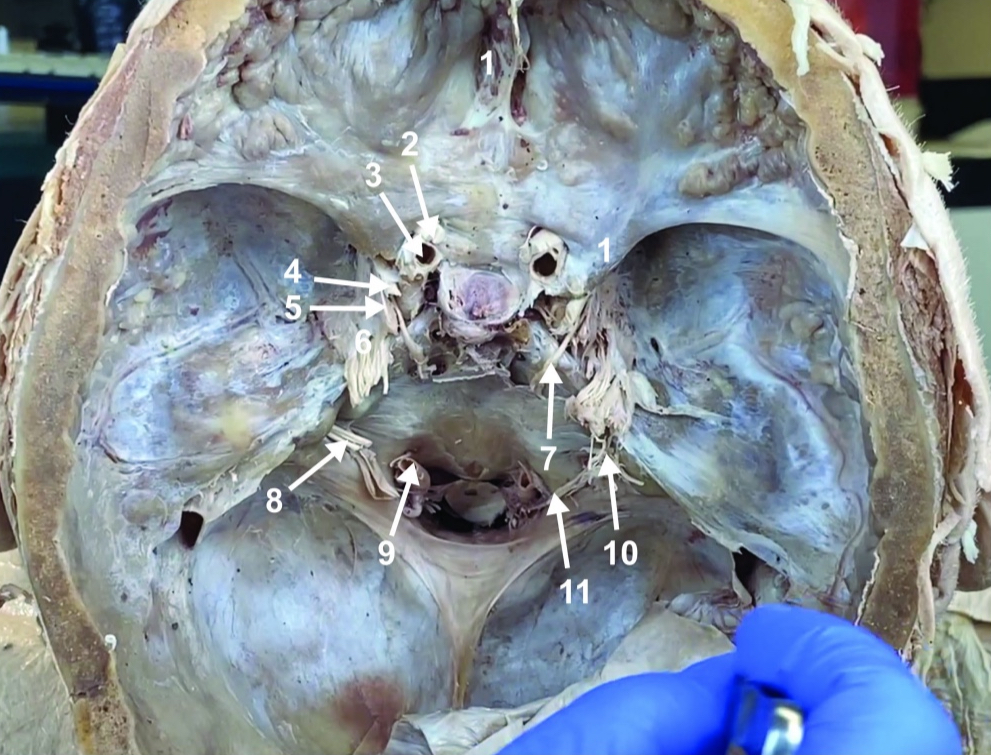

Foramen magnum

ID structure

Foramen ovale

ID structure

Foramen spinosum

ID structure

Cribiform plate

ID structure

Optic n. (CN II)

ID structure

Internal carotid a. (ICA)

ID structure

Occulomotor n. (CN III)

ID structure

Trochlear n. (CN IV)

ID structure

Trigeminal n. (CN V)

ID structure

Abducent n. (CN VI)

ID structure

Facial and vestibulocochlear n. (CN VII and VIII)

ID structure

Vertebral a.

ID structure

Glossopharyngeal and vagus n. (CN IX and X)

ID structure

Root of spinal accessory n. (root of CN XI)

ID structure

Ophthalmic division of CN V (CN V1)

ID structure

Maxillary division of CN V (CN V2)

ID structure

Mandibular division of CN V (CN V3)

ID structure

Foramen rotundum

ID structure

Foramen ovale

ID structure

Trochlear n. (CN IV)

ID structure

Abducent n. (CN VI)

ID structure